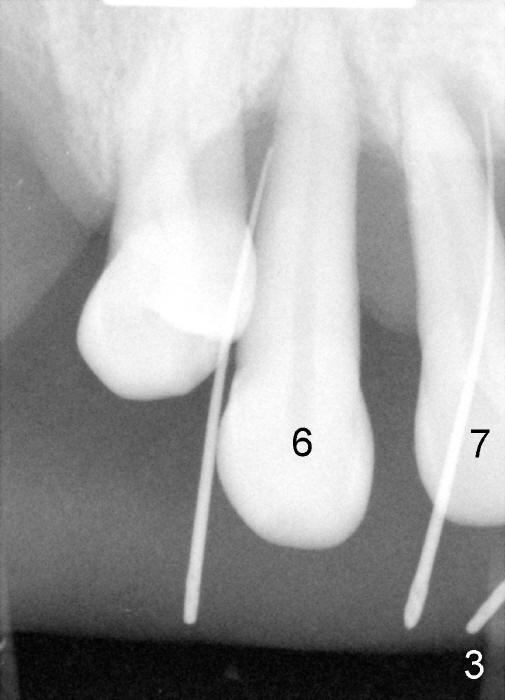

3. He has lost several upper teeth: #2,3,4,14 and 15.  The remaining teeth are loose, particularly #6,7, and 9 (Fig.1-4).  There are several treatment options for him.  Tell him that the doctor will discuss with him

6. Since the tooth # 6 shifts the most (Fig.1 arrow), it will be extracted first (the reason will be further explained in section #9), followed by thorough curettage, copious irrigation and soak with antibiotic